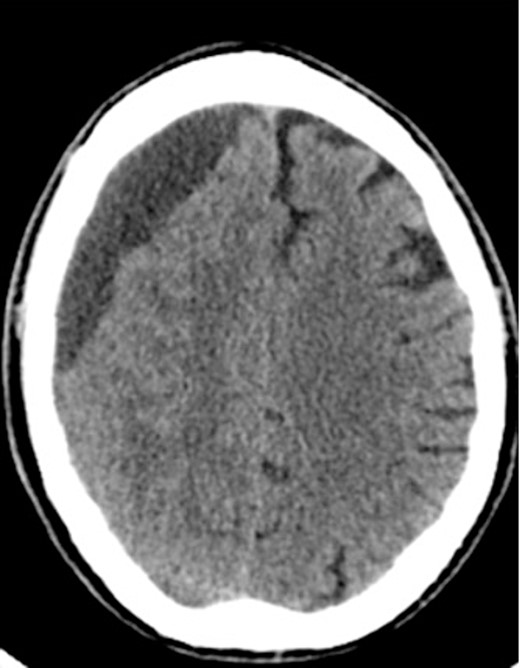

An 81-year-old male with a history of acute subdural hematoma, previously managed non-surgically, presented with worsened confusion and cognitive dysfunction. Repeat CT demonstrated expansion of right-sided subdural collection, consistent with cSDH (Fig. 4).

After the head was positioned in a supine neutral position on a horseshoe head holder, the AR system was used to overlay the hematoma and other relevant anatomy onto the patient’s head. Midline locations, vasculature and the blood collection were appreciated via AR overlay prior to marking an incision (Fig. 5). The AR overlay was then used to plan two separate linear incisions for two right-sided burr holes—one frontal and one parietal over the largest components of the hematoma as visualized with AR. A perforator drill was used to create the two burr holes which were widened with a burr and rongeurs. Beneath the dura, a hematoma was identified and its thick membrane layer was coagulated with bipolar cautery. The surgical sites were irrigated with saline to evacuate chronic blood. A ventriculostomy catheter was then placed into the subdural space at the frontal burr hole and tunneled lateral to the incisions. The burr holes were covered with titanium covers. There were no intraoperative complications, and the tolerated procedure well with improved cognitive function several days after surgery. Post-operative CT demonstrated significant interval decrease in hematoma volume and reduction in midline shift (Fig. 6).